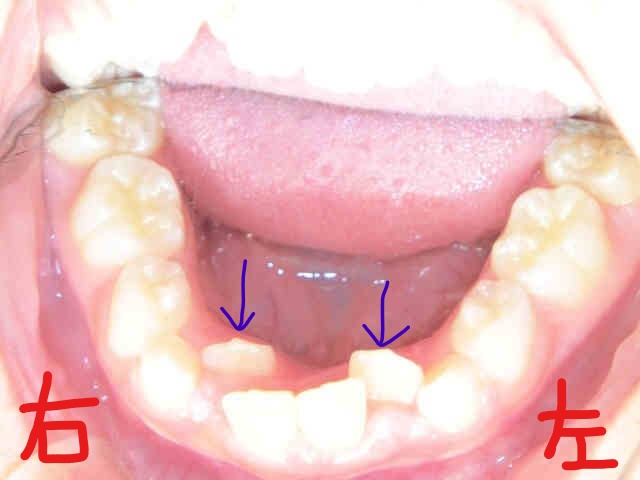

上記の写真は、下顎を上から見たものです。下顎前歯〈青色矢印の歯〉がかなり内側に生えていることがお分かりいただけます。